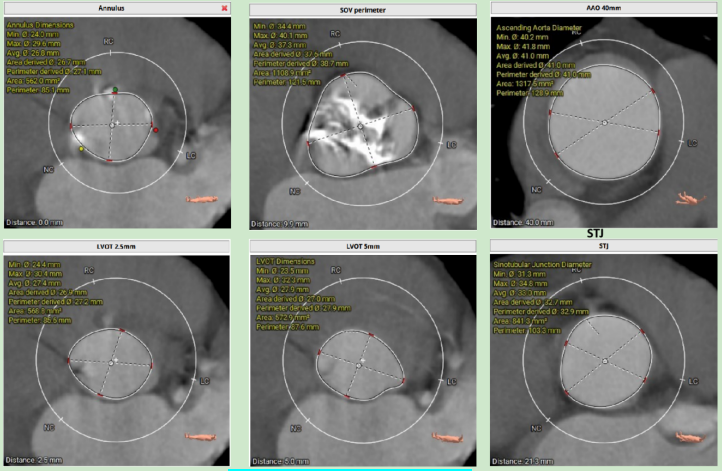

冠脈阻擋風(fēng)險(xiǎn)及左室大小評(píng)估

圖片